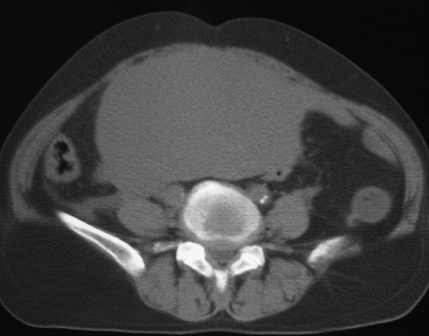

标题: CT11527:女56岁以右输尿管结石入院

女56岁以右输尿管结石入院

病灶位于下腹部盆腔,从子宫与膀胱明显受压后移看,应该来源于盆腹腔的占位,病灶实性部分密度均匀,左侧可见低密度灶,建议增强扫描,考虑:间叶性肿瘤,或硬纤维瘤,输尿管下段结石伴上段输尿管扩张

右侧盆腔占位,考虑来源于卵巢,囊腺瘤可能性大。

右侧输尿管结石。

1)盆腔占位性病变,考虑来源于卵巢,囊腺瘤可能性大。2)右侧输尿管第二狭窄处结石伴梗阻。

今天病人已经手术证实为右附件囊肿,右侧输尿管第二狭窄处结石伴梗阻!!!

[病理诊断] CT11527:右附件囊肿,右侧输尿管结石。